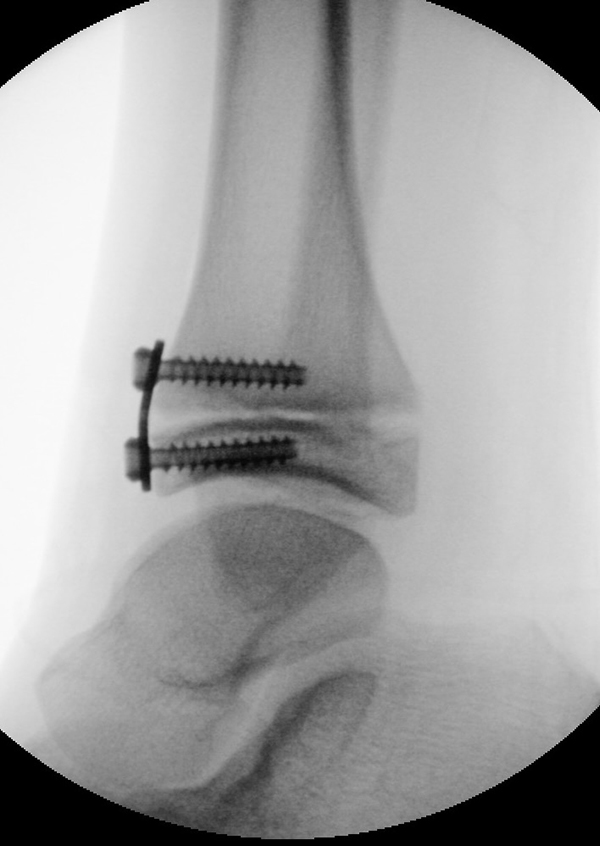

Wachstumslenkung mit moderner Klammer oder eight plate

Bei offenen Wachstumsfugen kann über eine Steuerung des Wachstums mit einer Klammer (Blount-Klammer/Flex Tack) oder kleinen Plättchen (Eight Plate) eine Korrektur von Achsabweichungen in der sagittalen und coronaren Ebene erreicht werden (Abb. 8). Der Hautschnitt beträgt ca. 1,5 - 2 cm und die so versorgten Kinder können ihre Extremität direkt postoperativ schmerzadaptiert voll belasten. Die wachstumslenkende Operation mit einer Klammer oder einem Plättchen besitzt ein enormes Korrekturpotential und erspart dem Kind oder Jugendlichen umfangreiche Umstellungsosteotomien und Plattenosteosynthesen, welche eine Schnittlänge von 15 cm und eine Entlastung des operierten Beines von 4-6 Wochen erforderlich machen.

Abb. 8 a-g: Genua vara prä- und postoperativ versorgt mit Flex Tacks (a-b) und ein Genu valgum versorgt mit Eight Plate an der medialen Femurkondyle (c); Spitzfuß bei congenitalem Klumpfuß und einem Flat Top Talus mit präoperativem Röntgenbild seitlich und der deutlich nach dorsal stehender Tibia(d); intraoperative Bilder der Epiphysiodese mittels Eight Plate zur Wachstumslenkung der distalen Tibia in die Extension (e-f) und postoperativer Verlauf nach sechs Monaten mit regelrecht stehender Tibia über dem Talus durch die distale Extension (g).

Zum Lesen der Bildbeschreibung und zur Vollansicht bitte die Bilder anklicken. Bilder: A. Helmers.